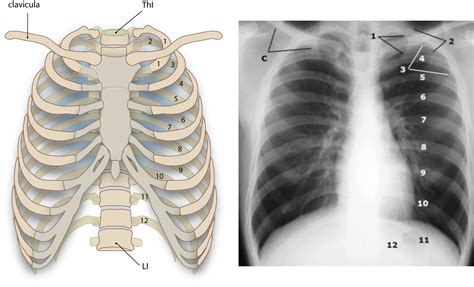

Let’s get down to the nitty-gritty of the os clavicula ’s anatomy, guys. The collarbone is a slender, S-shaped bone that sits right on top of your rib cage, just beneath your skin. It’s one of the most frequently fractured bones in the body, especially in active individuals, so knowing its structure is key. It has two main ends: the sternal end and the acromial end . The sternal end, the medial part, connects to the manubrium of the sternum (your breastbone) at the sternoclavicular joint. This joint is pretty special because it’s one of the few places where a long bone articulates with the axial skeleton. The acromial end, the lateral part, connects to the acromion, which is part of the scapula (your shoulder blade), forming the acromioclavicular (AC) joint. This connection is vital for shoulder girdle mobility.